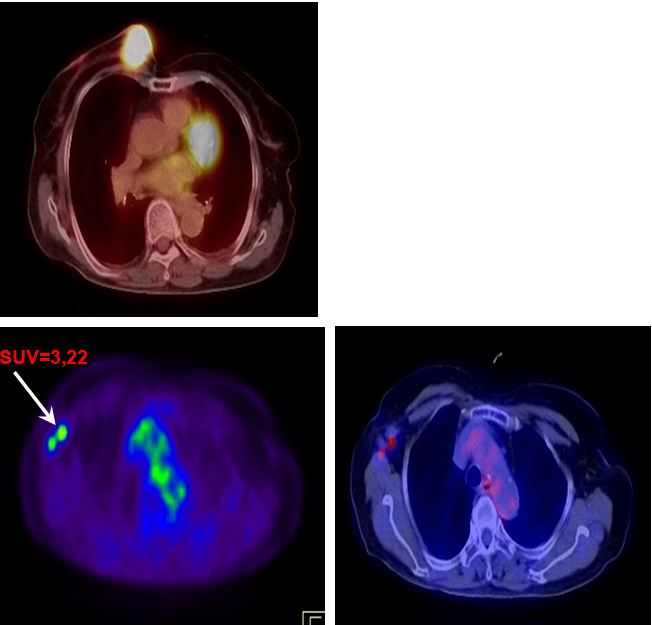

BN ung thư vú có di căn hạch nách phải

PET/CT K vú di căn xương,hạch nách